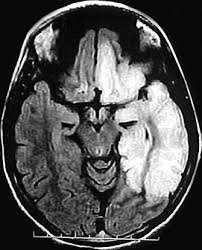

Chikungunya, de acordo com este estudo, parece ter maior probabilidade de causar inflamação e inchaço no cérebro (encefalite) e medula espinhal (mielite) (+)

Já o AVC, que poderia ser causado por qualquer um dos vírus isoladamente, parece ter mais chance de ocorrer em pacientes infectados com os dois vírus juntos.

Um AVC ocorre quando uma das artérias que fornecem sangue ao cérebro fica bloqueada (+)

Siga 👇 Exame de imagem mostra cortes do cérebro com algumas áreas